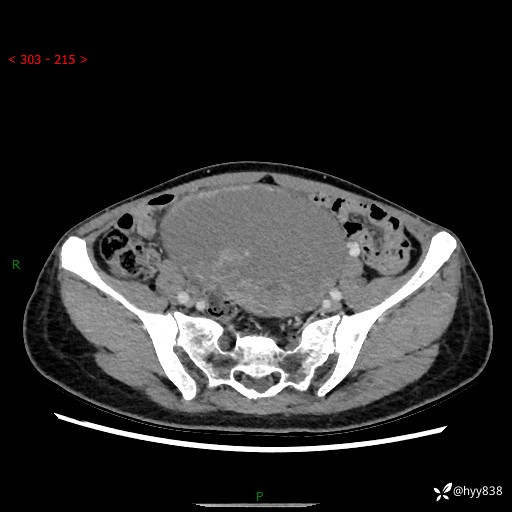

【患者信息】:女,50岁

【主诉】:外院超声发现腹盆肿块,为进一步诊治来我院,门诊已“盆腔肿块”收入院。

腹盆CT平扫+增强

【临床诊断】:盆腔肿瘤